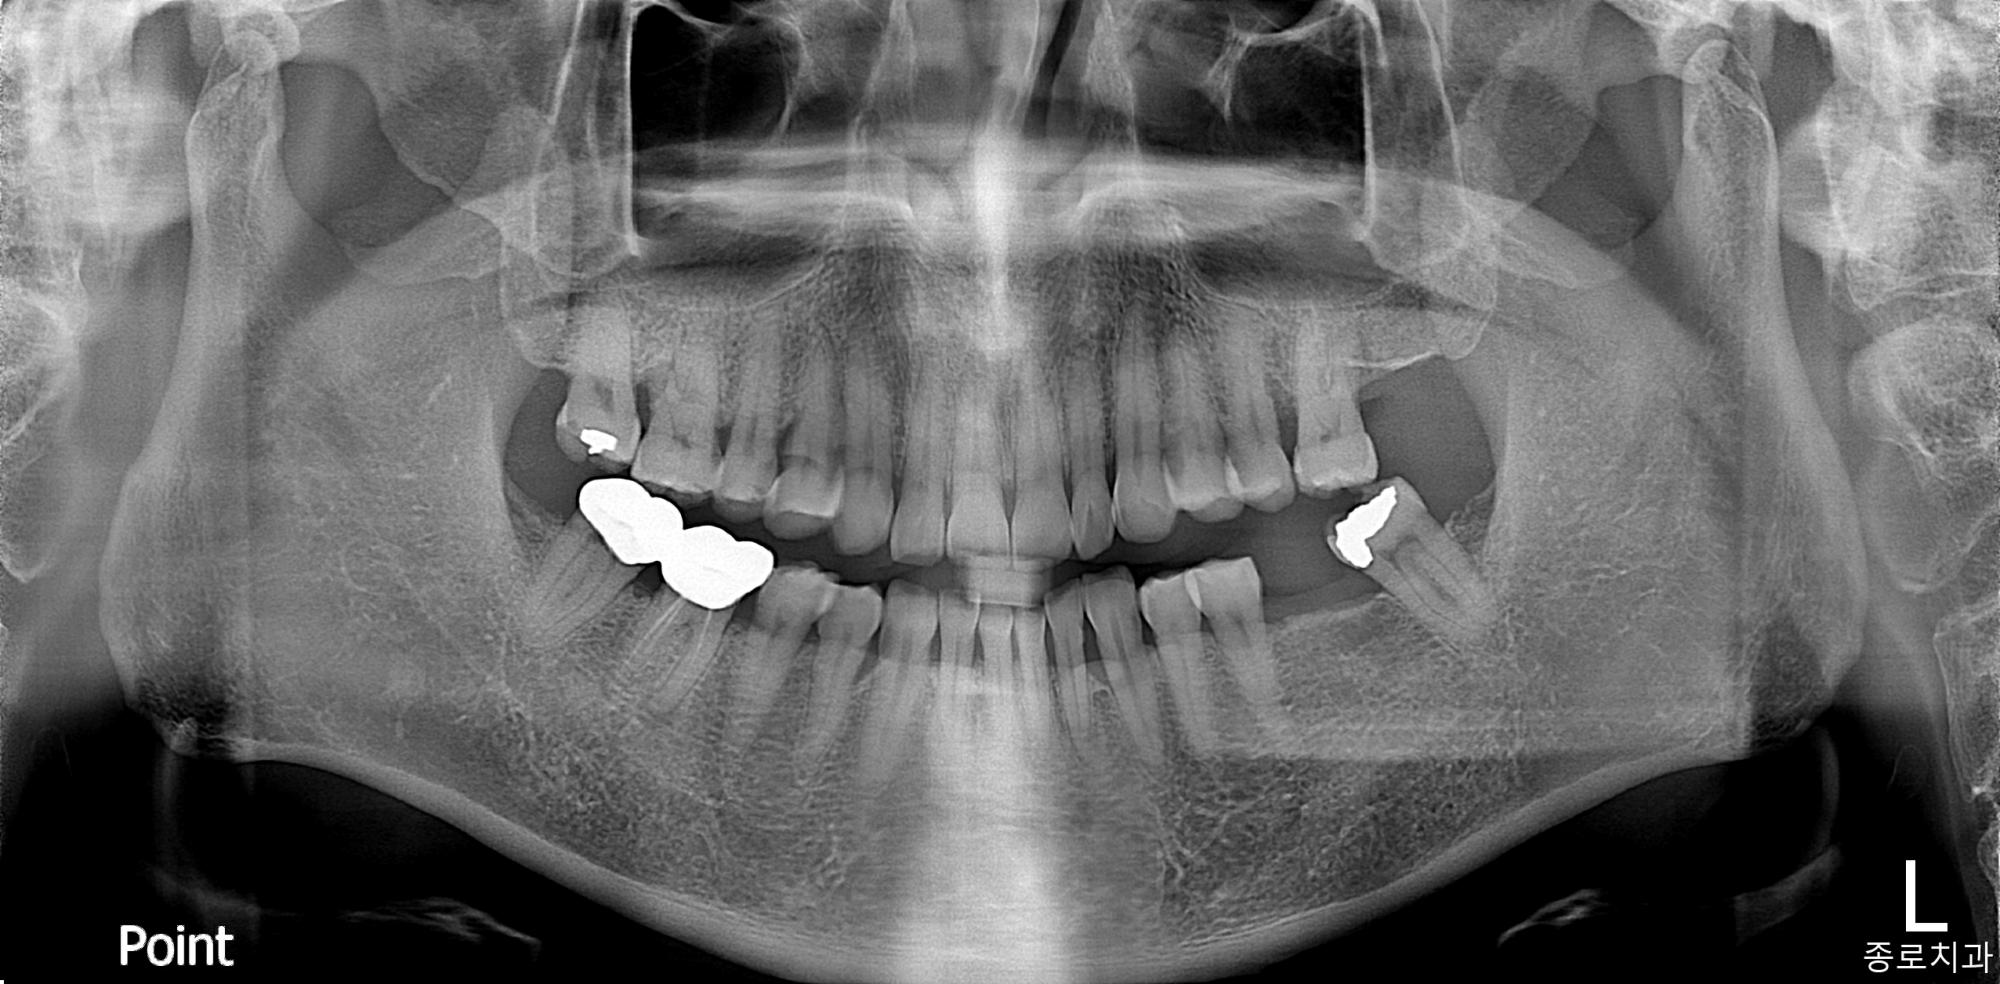

전/후사진

전/후 사진갤러리